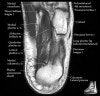

- Coronal section

The coronal oblique T1 sequence follows the tendons of the ankle around the malleolar turns and also evaluates the medial ankle ligaments.

The coronal oblique PD fat suppressed sequence follows the tendons of the ankle around the malleolar turns and is particularly important in evaluation of the Posterior tibialis tendon.

Bone and marrow

Talar dome

Deltoid ligament

Tendons in arch

Plantar fascia

Troubleshoot ligaments